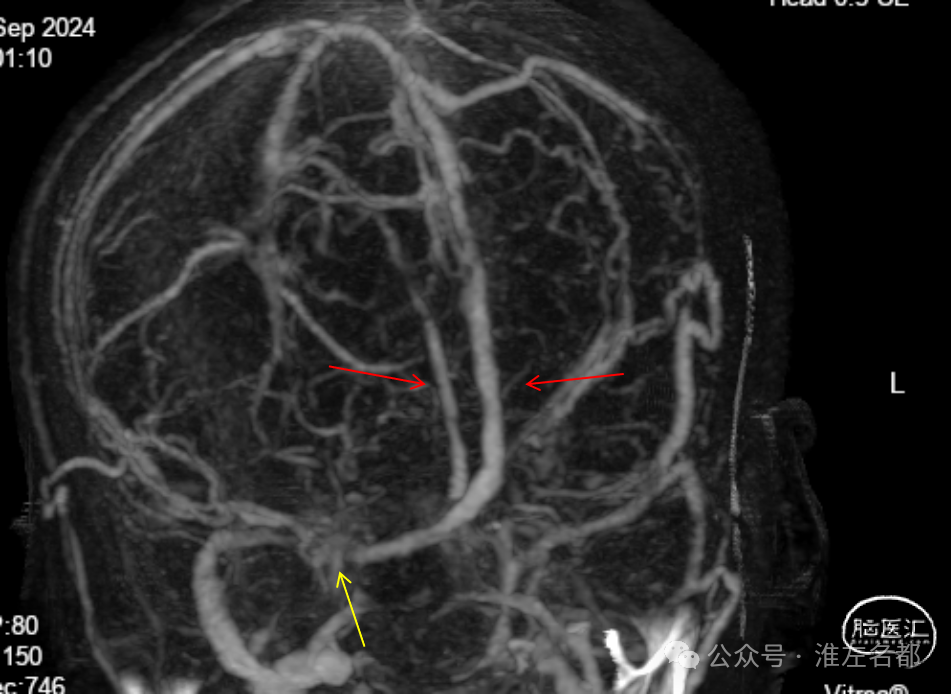

复杂静脉窦血栓介入治疗:直窦新近血栓合并上矢状窦和优势横窦-乙状窦慢性血栓

CTV:左侧横窦-乙状窦细小,右侧横窦充盈缺损,深部静脉系统未见显影,上矢状窦显影不清晰。

增强MRV:左侧横窦-乙状窦显影纤细;上矢状窦和右侧横窦-乙状窦充盈缺损;脑深部静脉和直窦未见显影。

右侧颈动脉造影(正侧位):上矢状窦和直窦未见显影;右侧横窦和乙状窦少许显影。

左侧颈动脉造影(正侧位):上矢状窦前部少许显影,直窦未见显影,左侧横窦和乙状窦显影纤细。

介入治疗后右侧颈动脉造影:上矢状窦、直窦和右侧横窦-乙状窦均见显影,右侧横窦局部狭窄明显。

CTV:上矢状窦、直窦、右侧横窦-乙状窦再通显影,右侧横窦局部管腔狭窄明显。